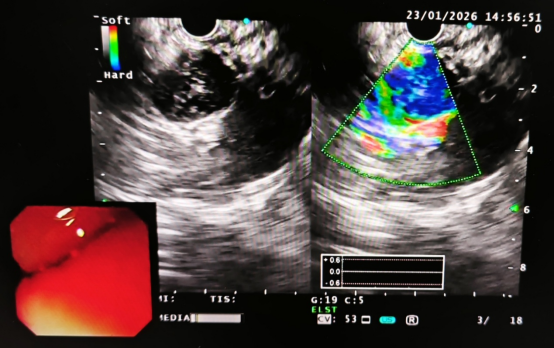

术前超声胃镜检查发现复发的胃间质瘤